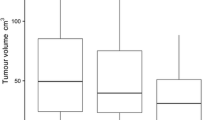

Monoparametric analysis

Hounsfield unit attenuation and iodine concentration were both significantly higher in metastatic (Attenuation: − 80.1 ± 192.0 HU; IC: 1.6 ± 0.5 mg/ml) than in benign lung nodules (Attenuation: − 170.5 ± 173.5 HU; IC: 1.4 ± 0.5 mg/ml; both p≤0.05). However, for both parameters, a significant data overlap was observed between the two lesion types (Fig. 3). Consequently, area under the ROC analysis revealed a low AUC of 0.67 and 0.58 for HU and IC, respectively, regarding benign and metastatic nodule differentiation. Pertaining to texture features, kurtosis, skewness and uniformity derived from CI showed significant differences between benign nodules and lung metastases, while for iodine map derived features, significant differences were found for entropy, kurtosis, uniformity and UPP; Table 2 shows the comparison of mean values of all tested features between benign and metastatic lung nodules. Figure 4 depicts exemplary cases of metastatic and benign lung nodules with entropy feature maps, which was the most powerful iodine map-derived feature.